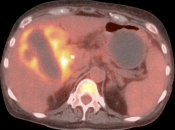

- Fusion of Images

4. Abdomen & Pelvis

- Liver Ablation